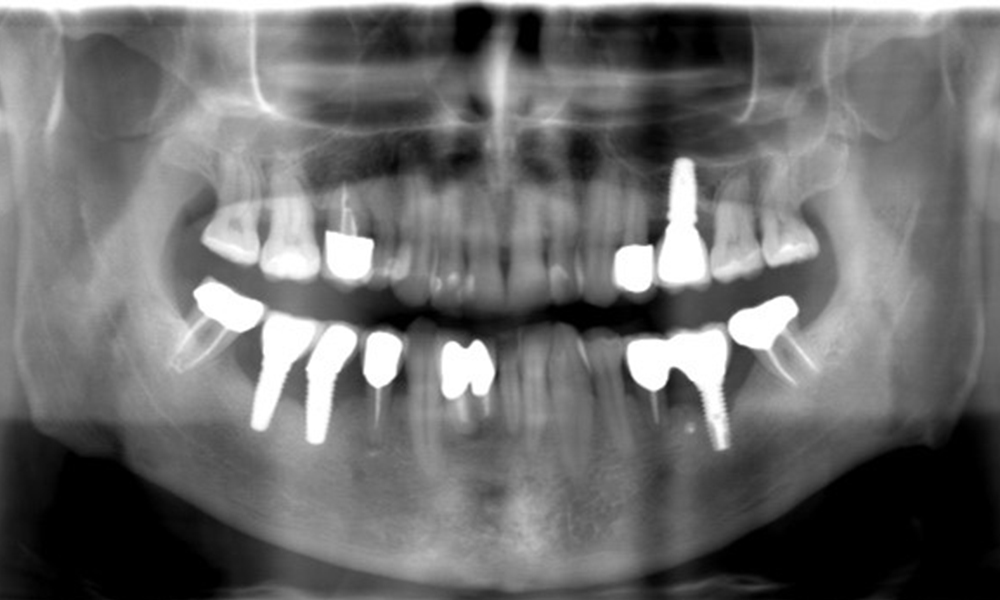

The X-ray images show the progression of bone loss. OPG from 29.06.2020 (left) and OPG from 26.02.2024 (right).

The X-ray images show the progression of bone loss.